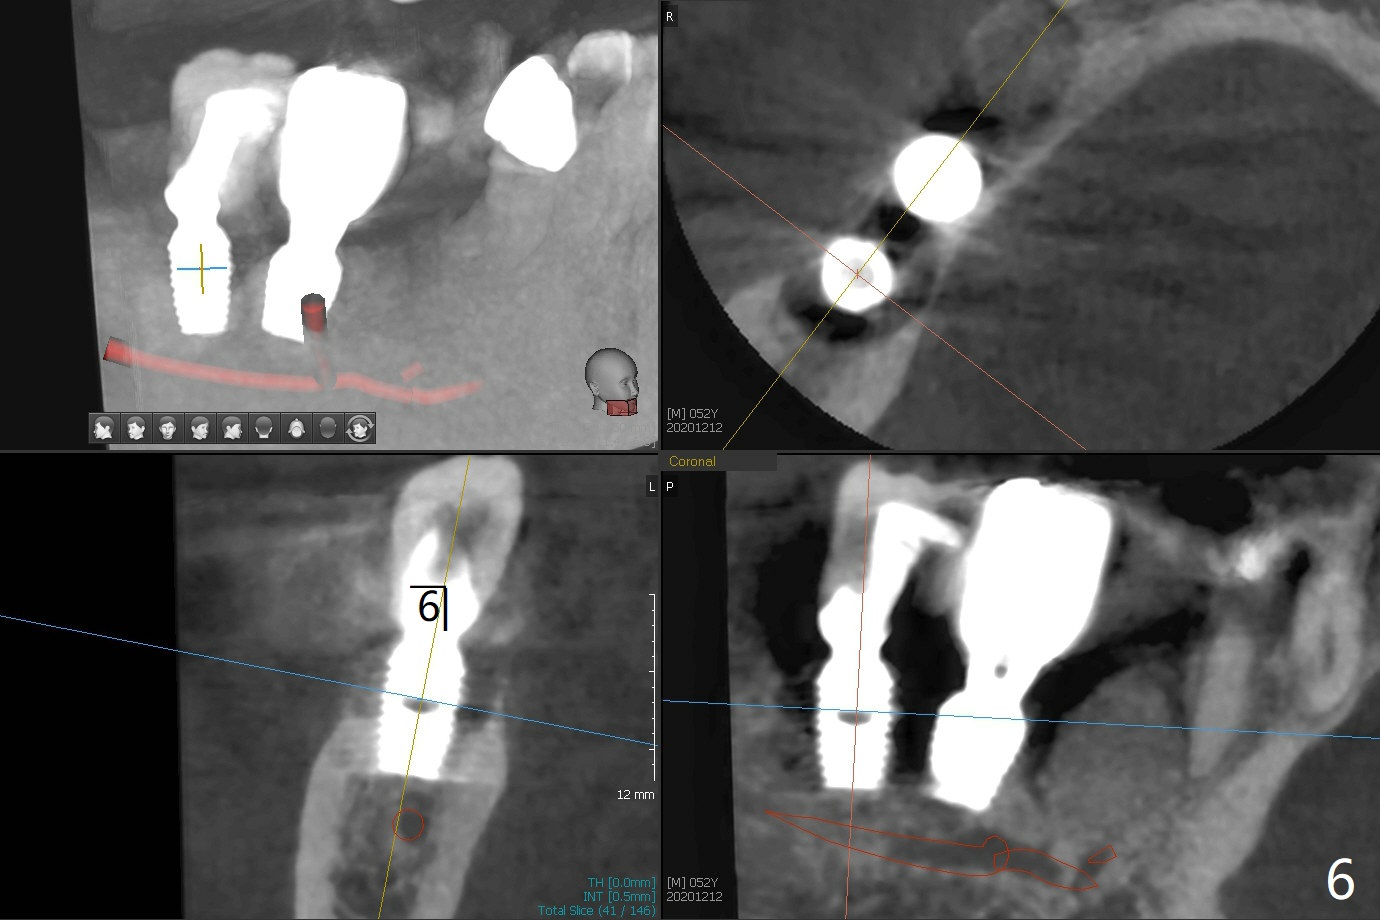

52岁男右下4植体脱落三天回到诊所(图一),植牙创尚未闭锁,顺着开口去除肉芽组织,冲洗,充填皮质骨骨粉(图二,三),颊侧骨板外形恢复(图四,五:*)。重新植入UF植体(5)颊侧还有薄颊侧骨板(图五:>),而6植体周围骨质吸收(图六),植骨好像有希望,植体还在牙槽骨范围,也有利于5植体生存。术后12天伤口愈合(图七)。尽管使用水枪,仍有6植体周围炎,需要治疗(图八)。由于右侧手术,病人不得不用左侧咀嚼,他认为左下4松动,无法挽救。术后3.5个月牙槽嵴和角化龈缩小(图九),需要切开使用导板。术后3.5个月骨粉高度明显下降(图十)。只能植入4x8.5毫米植体(图十一)。